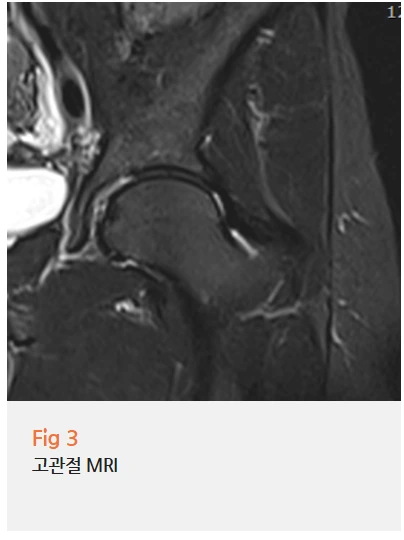

그래서 저는 당일 허리와 고관절 MRI를 모두 촬영하자고 제안드렸어요.

요추 추간판 탈출증 소견이 확인됐고,

하지 근전도 검사에서는 만성 요추 신경근병증 소견도 함께 나왔어요.

%EA%B7%B8%EB%A6%BC2.png?type=w966

반면 고관절 자체에는 구조적인 문제가 없었죠.

%EA%B7%B8%EB%A6%BC3.png?type=w966

그러니까 고관절이 아팠던 게 허리에서 내려오는 신경 압박 때문이었던 거예요.